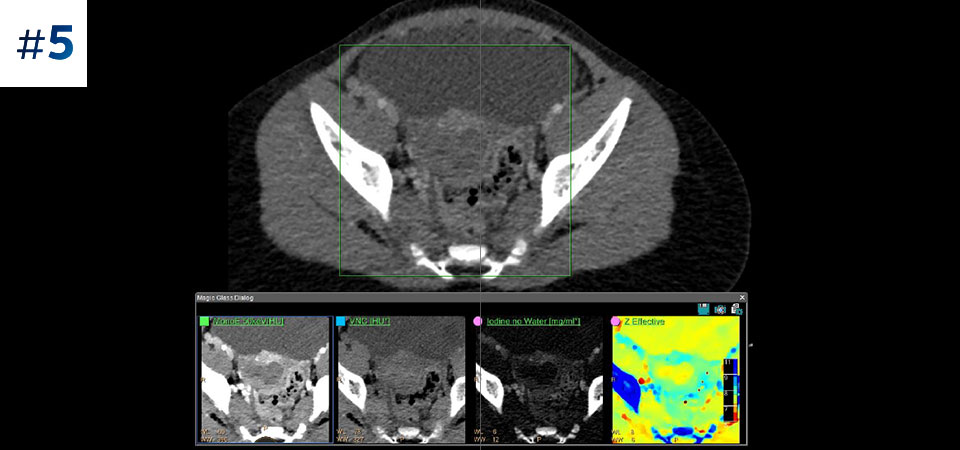

通常どおりにスキャン いつでもどの患者に対しても、1回の高速な低線量スキャンで標準データおよびスペクトラルデータを取得できます。

常に使用可能 スペクトラルデータは常に100%使用可能であり、検査結果はいつでも、オンデマンドだけでなく、レトロスペクティブに取得することもできます。

フォローアップ検査の削減 組織の特性評価と視覚化が改善されることにより、患者の検査が最適でなかった場合や、偶発病変が見つかった場合に、フォローアップスキャンを行う必要性が低減される可能性があります。